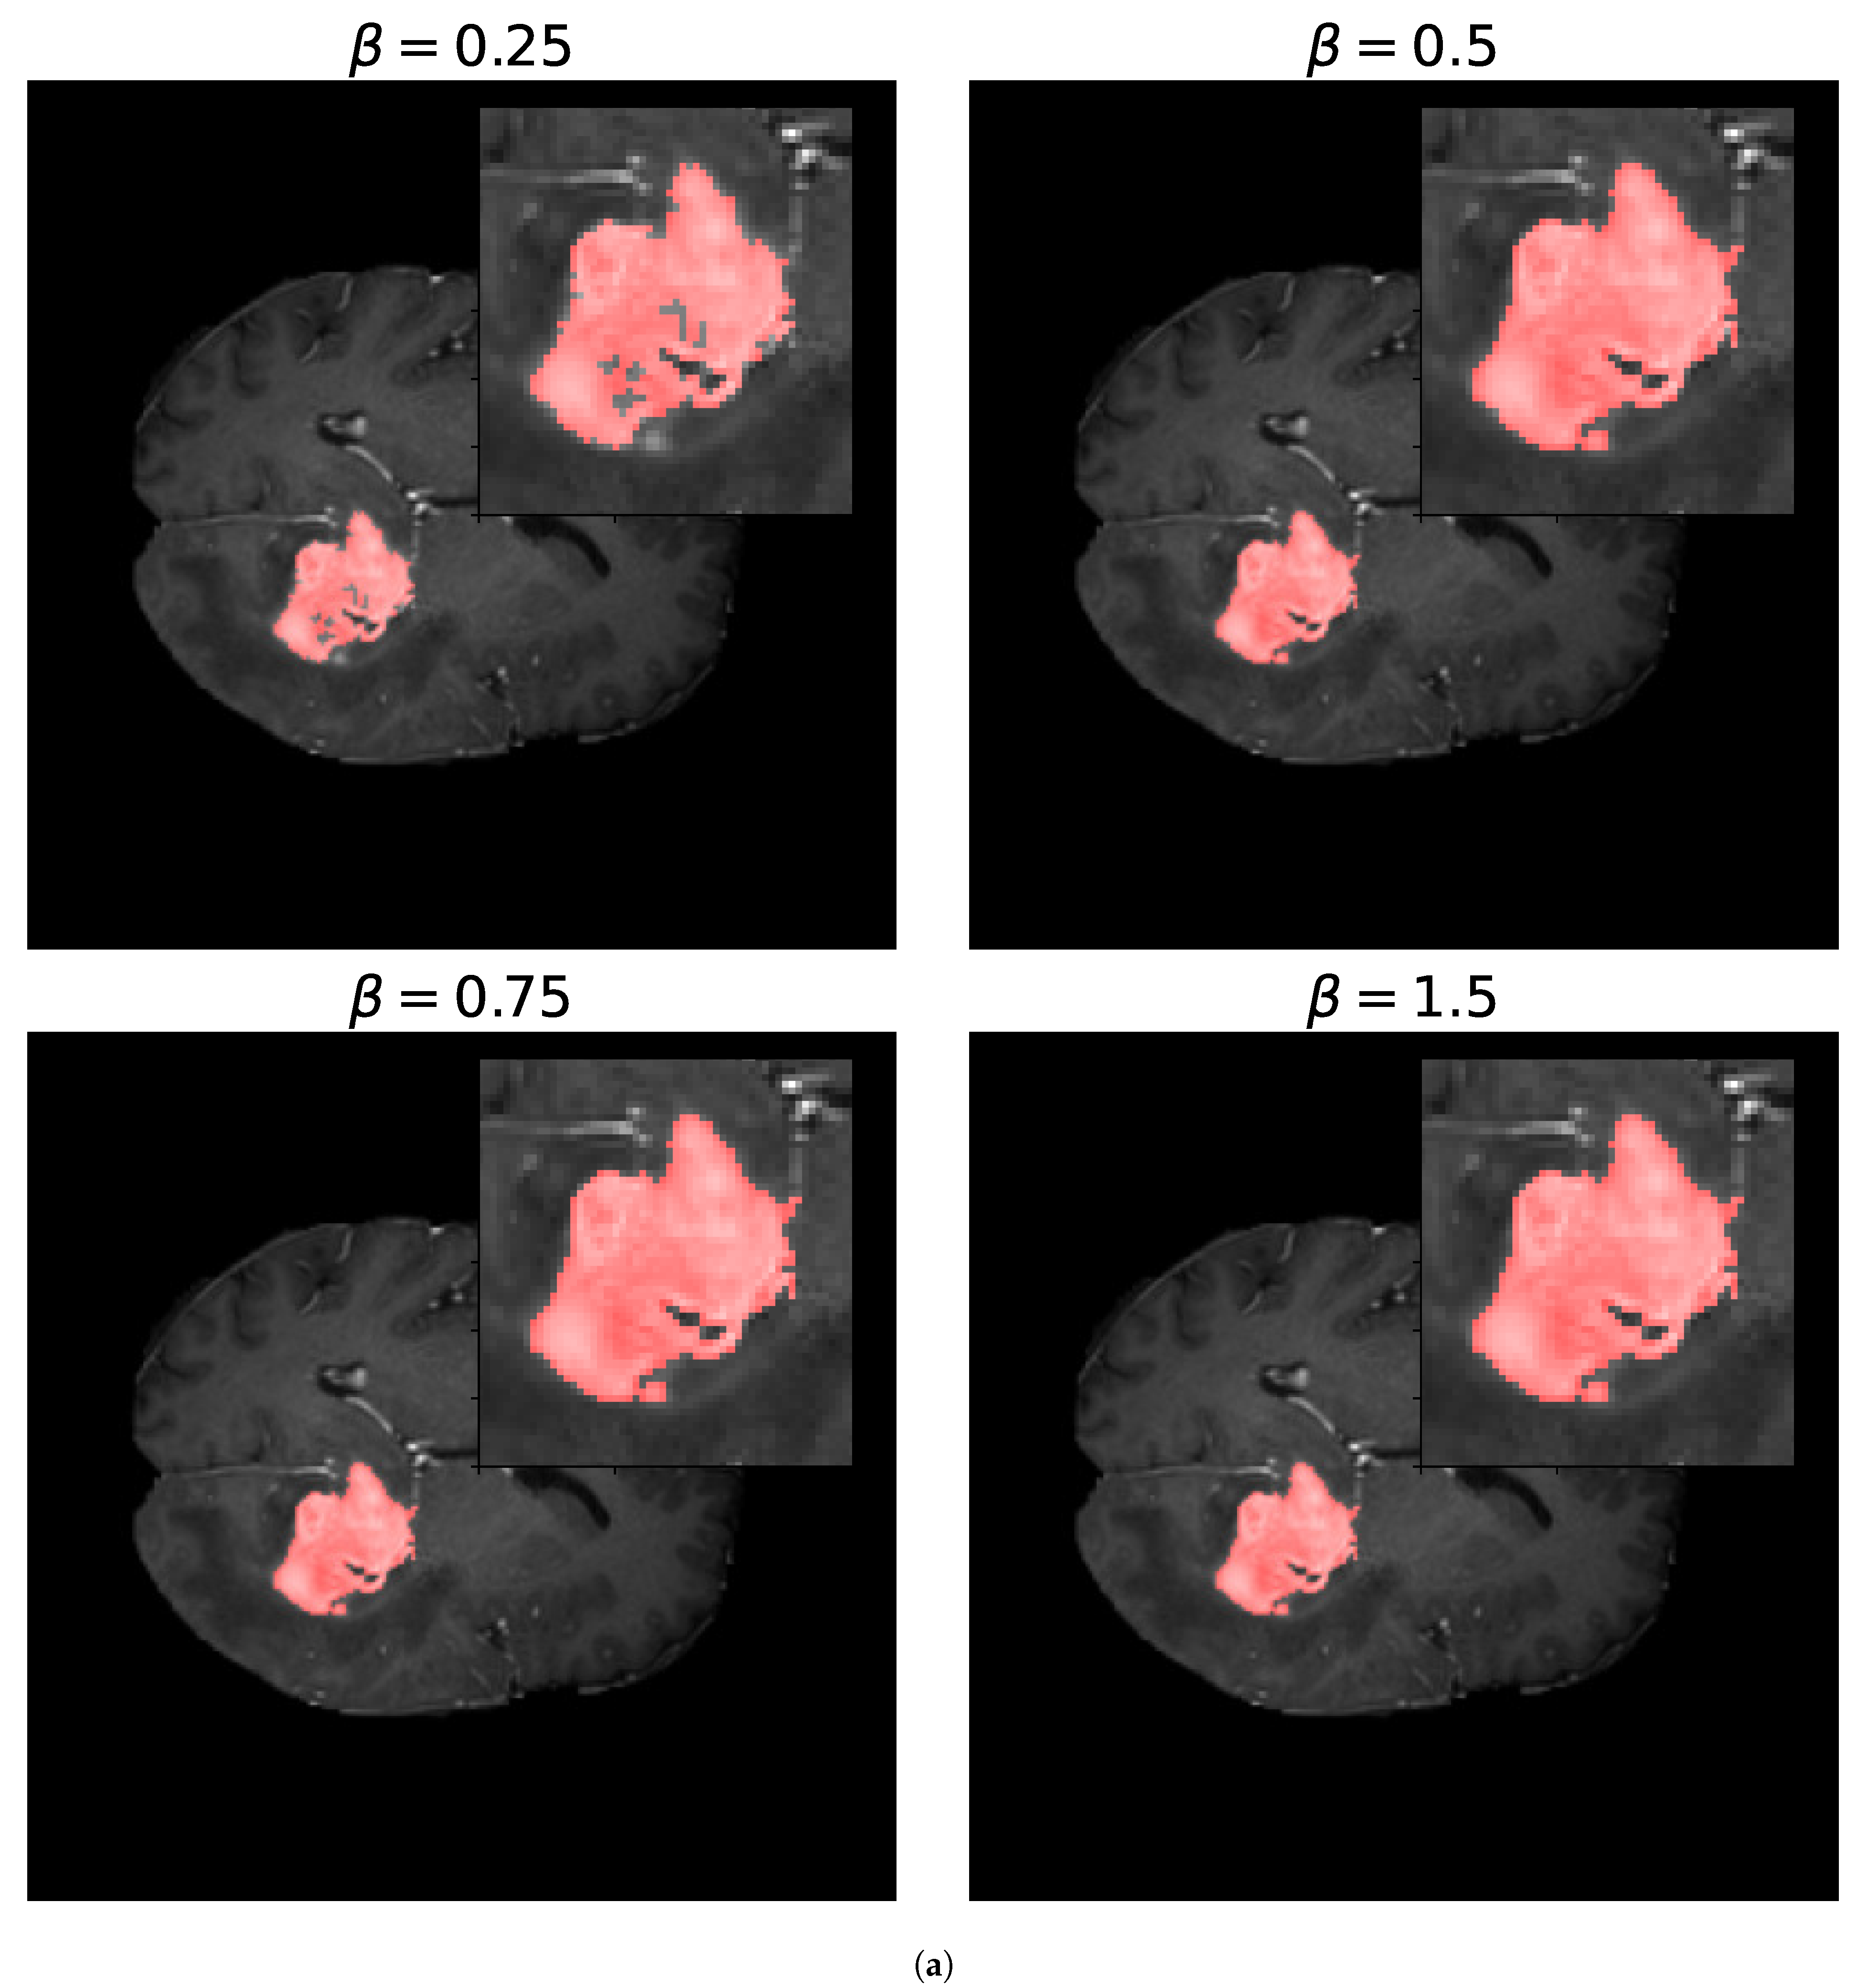

For the -measure, we can see in Figure 11 the binary masks obtained for different values of for the core and whole tumor. For the case of the core tumor, we can observe that, for , we obtain areas of misclassified pixels in the tumor region. This can also be seen from Table 4, where the number of false negatives is larger and the number of false positives is smaller compared to the results obtained for larger values of . If we recall (31), we can see that, for low values of , the false negatives are multiplied by a factor of , thus having a smaller weight compared to the false positives. As we increase the value of , we can notice from both Table 4 and Figure 11 that modifying the value of has no impact on the resulting binary mask. This also holds true for the whole tumor as no difference can be noticed in the results obtained for different values of . Finally, in Figure 12, we see the loss reported for different values of , where the loss equal to 1 represents a perfect overlap. First, it can be noticed that we obtain the higher value of the loss for , meaning that this should be the most accurate result, which is balanced anyway by the fact that we obtain a larger number of false negatives. Again, we observe that this can be obtained from (31), where low values of reduce the impact of a large number of false negatives on the resulting loss. Secondly, we observe that the loss decreases for larger values of . This behavior arises because the loss is inversely proportional to , while the resulting segmentation masks remain unchanged, as shown in Table 4. This shows that the -measure may not be a reliable metric for these types of segmentation masks and this segmentation method, and that modifying the value of provides no advantage.

Figure 11.

Segmentation masks obtained for the -loss metric. (a) Shows the segmentation masks obtained for and for the core tumor and (b) shows the segmentation masks obtained using the same values of for the whole tumor. Both images consist of pixels. For the optimization procedure, we set and . In both cases, we considered 300 iterations of the optimization algorithm. In (a), we can observe that, for , the resulting segmentation masks display areas of misclassified pixels, while, for larger values of , the resulting segmentation mask does not differ. In (b), no zoomed area is shown as the segmentation masks display no visible differences for the different values of . This is also evident in Table 4 by observing the number of false positives (FPs), false negatives (FNs), and true positives (TPs) obtained for both images.

Parameters obtained for the -measure for different values of . The loss reported is 1 for perfect overlap and 0 for complete deviation. The numbers of false positives (FPs), false negatives (FNs), and true positives (TPs) are presented for the resulting segmentation masks for each value of .